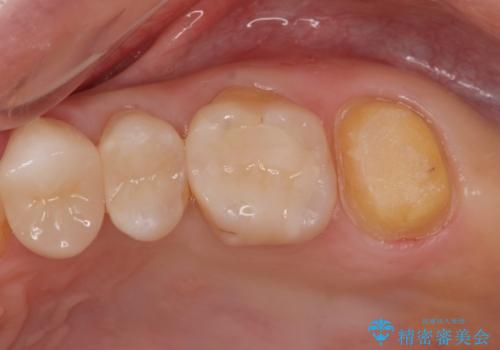

- 銀歯を無くしたいとの事で来院。

拡大鏡下でメタルを除去し虫歯がないことを確認してから白い詰め物、被せ物で治療を行いました。

適合の良い詰め物、被せ物が入りました。